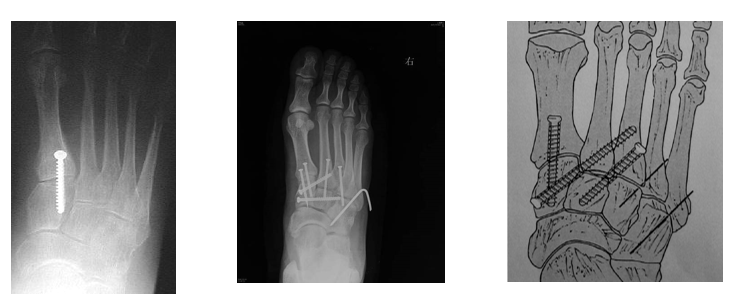

内固定选择1、克氏针:优点是手术简单、时间短、对周围组织损伤小,缺点是固定不坚强、复位丢失等情况时有发生。2、可吸收螺钉:优点是不需行二次手术取出内固定物,缺点是固定强度不及传统螺钉3、小螺钉系统:经典 --- 3.0mm、3.5mm、4.0mm4、空心螺钉:3.0mm、4.0mm、4.3mm 、4.5mm5、微型钢板:跨关节固定,对于严重的跖骨粉碎性骨折的患者,螺钉无法固定时,建议选择微型钢板桥接固定6、骑缝钉

Lisfranc损伤骨折复位标准:1、C形臂透视显示正、侧、斜位均为正常解剖复位2、如复位后第1、2跖骨基底间隙和内、中楔骨间隙<2mm,跖跗骨轴线<15°为近解剖复位,可以接受,超过这个范围的移位则无法接受3、复位好后,沿第一跖骨轴线向内侧楔骨逆行拧入一枚4.0mm皮质骨螺钉。螺钉由关节远侧1.5-2.0cm处进入,平行于足底或略向跖侧。

4、从内侧楔骨向第二跖骨置入一枚螺钉,重建韧带。螺钉自内侧楔骨近端的背侧置入,指向第二跖骨背侧皮质的下方,螺钉应通过4层皮质,确保对第二跖骨的双皮质固定

术后管理石膏固定4~6周;如果固定稳定,术后两周可开始功能锻炼,4~6周部分负重,六周后完全负重;术后6~8周可拔去克氏针,术后3~4月可取出螺钉。有些人主张若无症状出现,可无限期地留置螺钉于体内